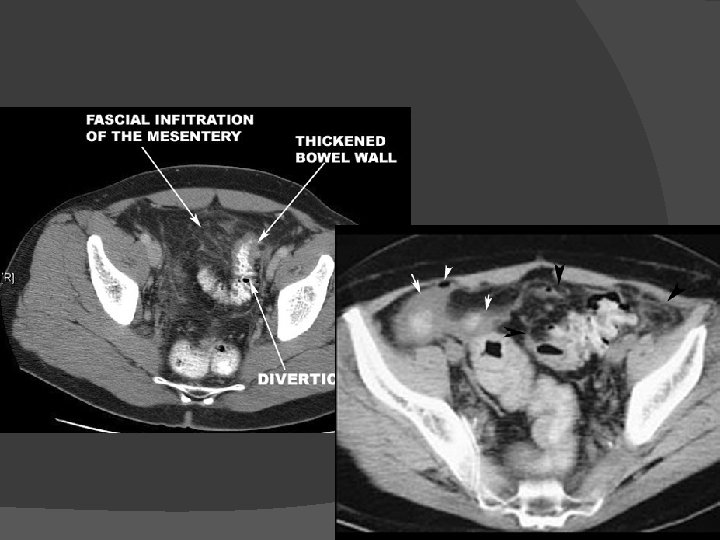

Diverticulitis Diverticulosis